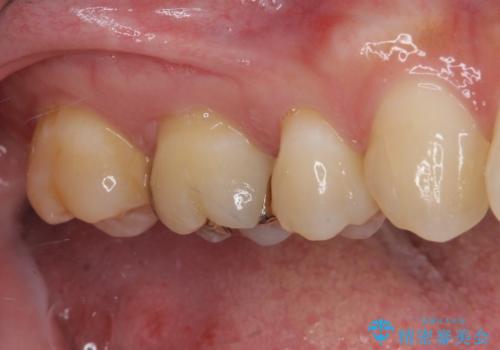

- 奥歯がしみて激痛が続くとのことで来院された患者様です。

診査の結果、不適合な銀歯の隙間からむし歯が進行しており、更には頬側、口蓋側ともに歯肉縁付近に強い知覚過敏症状が認められました。

健全歯質が多いため、インレーおよびむし歯を除去した上で知覚過敏を緩和させる処置を行うことが望ましいと判断されましたが、知覚過敏の症状が一向に改善されないため、全体をセラミッククラウンで補綴することとしました。